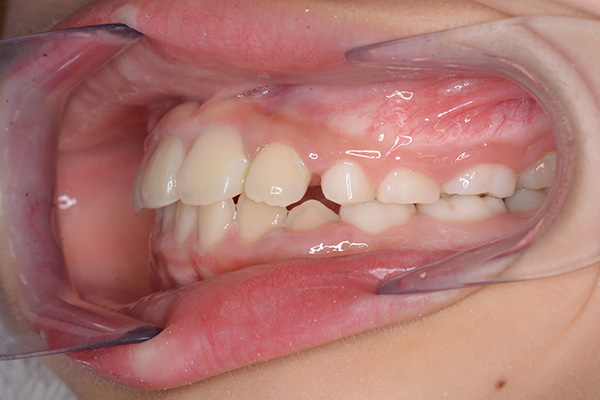

動的治療開始前(9歳7ヵ月)

動的治療開始前

(9歳7ヵ月)

口腔内所見 over jet -2.5mm、over bite 2.0mm、大臼歯関係はⅠ級 。Hellmanのdental ageはⅡCであり前歯部は反対咬合を呈していた。